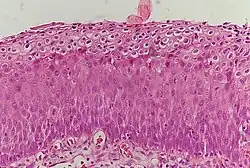

_normal_squamous_epithelium.jpg)

Historically, abnormal changes of cervical epithelial cells were described as mild, moderate, or severe epithelial dysplasia. In 1988 the National Cancer Institute developed "The Bethesda System for Reporting Cervical/Vaginal Cytologic Diagnoses".[12] This system provides a uniform way to describe abnormal epithelial cells and determine specimen quality, thus providing clear guidance for clinical management. These abnormalities were classified as squamous or glandular and then further classified by the stage of dysplasia: atypical cells, mild, moderate, severe, and carcinoma.[13]

CIN is classified in grades:[14]

| Histology Grade | Corresponding Cytology | Description | Image |

|---|---|---|---|

| CIN 1 (Grade I) | Low-grade squamous intraepithelial lesion (LSIL) |

|

%252C_Cervical_Biopsy_(3776284166).jpg)

|

| CIN 2/3 | High-grade squamous intraepithelial lesion (HSIL) |

|

|

| CIN 2 (Grade II) |

|

_CIN2.jpg) | |

| CIN 3 (Grade III) |

|

|